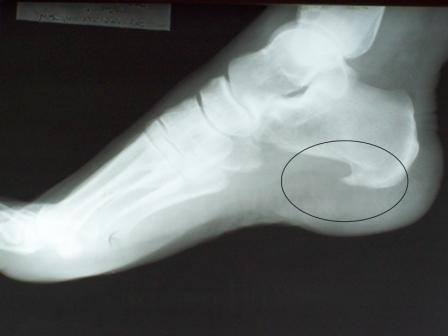

Esporão de Calcâneo

É uma formação óssea que ocorre no calcâneo (osso da base do calcanhar). Ao longo dos anos pequenos fragmentos ósseos resultado do desgaste do corpo, aglomeram-se e formam uma espícula, também conhecida por "esporão". que causam fortes dores nos pés.

A dor só ocorre quando é feito o apoio de carga ou pressão no local. Está relacionado também com obesidade e com o aumento súbito de atividades diárias.

A cirurgia para retirada do esporão só é considerada em casos extremamente dolorosos que não melhoram com o tratamento conservador.

eralmente o problema é bem controlado com a fisioterapia associada ao uso de palmilhas e calcanheiras de silicone, afim de eliminar a pressão do corpo exercida naquele ponto.